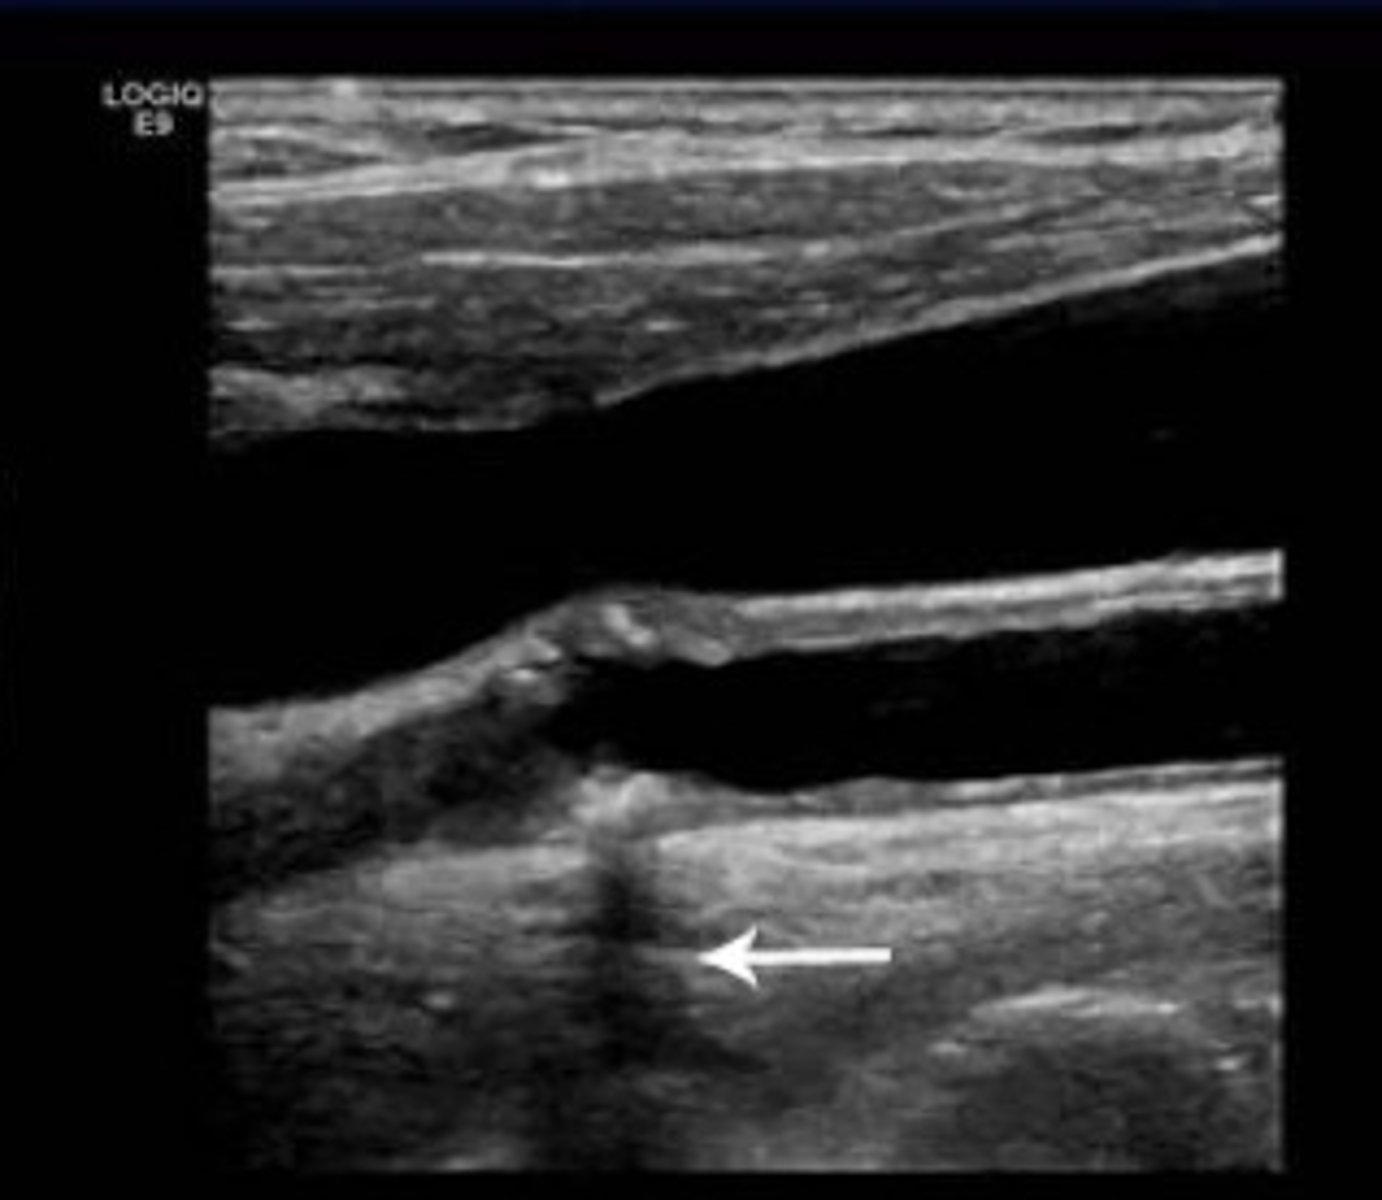

In this image of an artery there is a calcification with a dark vertical band extending beyond it. Which explanation best describes the etiology of the dark bend?

Reduction in signal amplitude in tissue distal to a highly attenuating or reflecting object

<p>Reduction in signal amplitude in tissue distal to a highly attenuating or reflecting object</p>